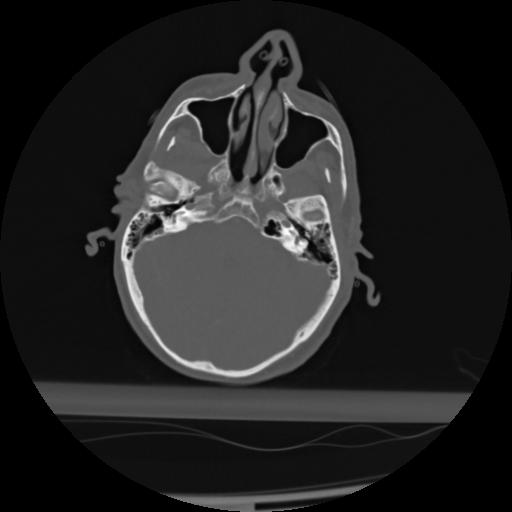

21 ANGIO,CE,Axial,3.0,ANGIO,,